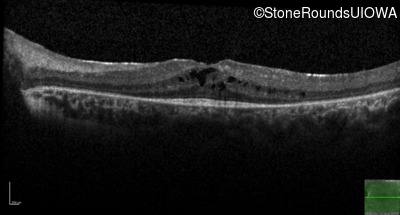

Age at visit: 9 years

Age at visit: 10 years